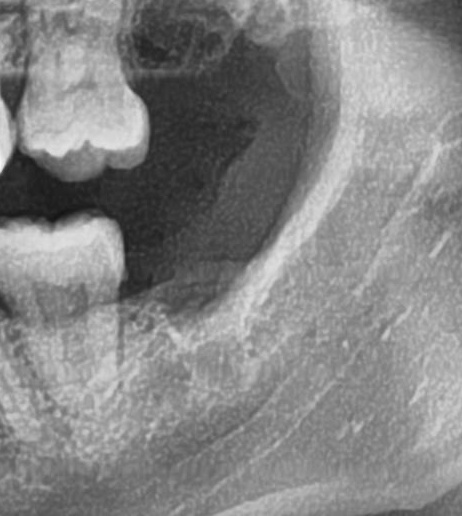

次にパノラマ写真を撮影してみると、左下の親知らずは手前の歯と並んでまっすぐに生えているのが確認できました。

親知らずが生えている位置が、神経に近い、あるいは神経に当たっている場合は、大きな病院に紹介する場合もあります。

親知らずの根っこは下歯槽神経からは十分距離があるようです。